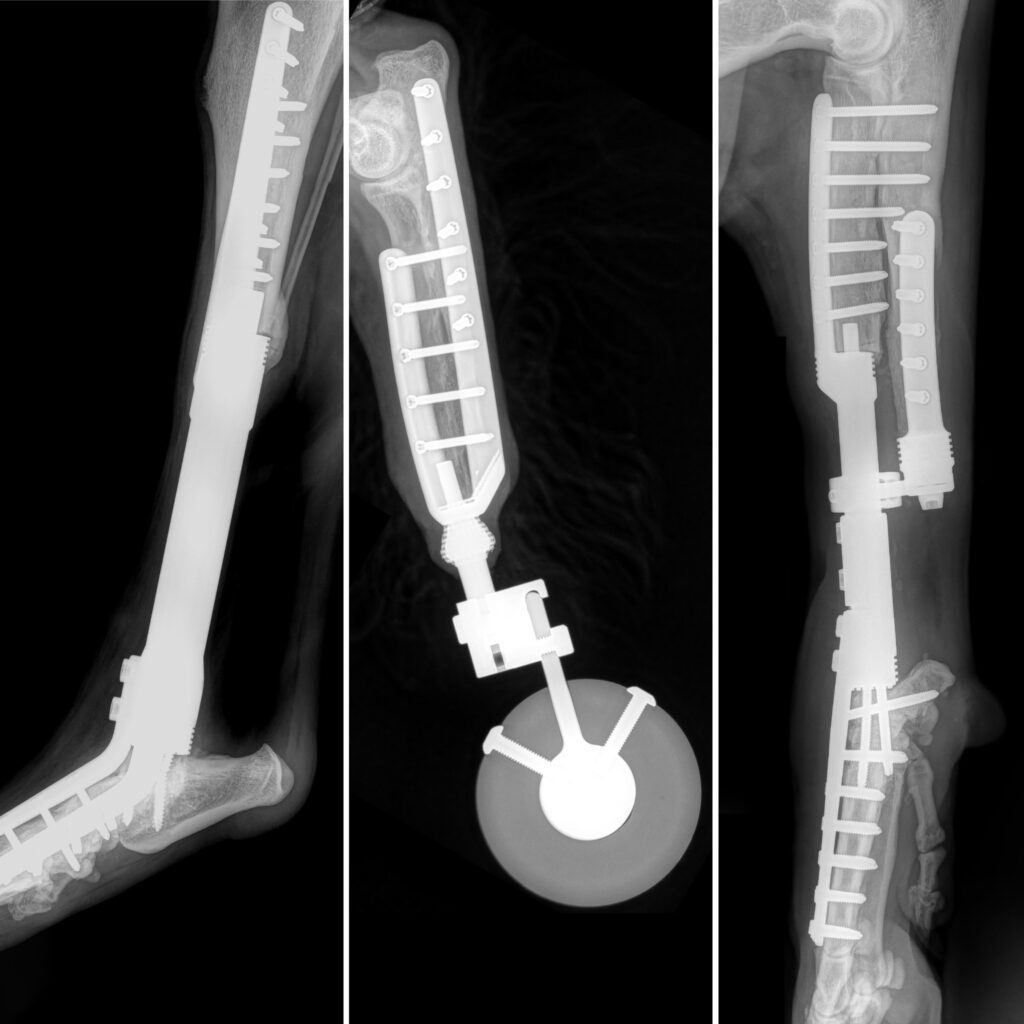

Limb sparing/salvage

Unique options to Fitzpatrick Referrals in limb sparing and salvage for treating trauma and cancer in the forelimb or hind limb.

Sprout’s complex fracture repairs & custom solution

PATIENT STORY

Pablo’s bone transplant

Major Tom’s osteosarcoma

Sunny’s rotating hinge total knee replacement